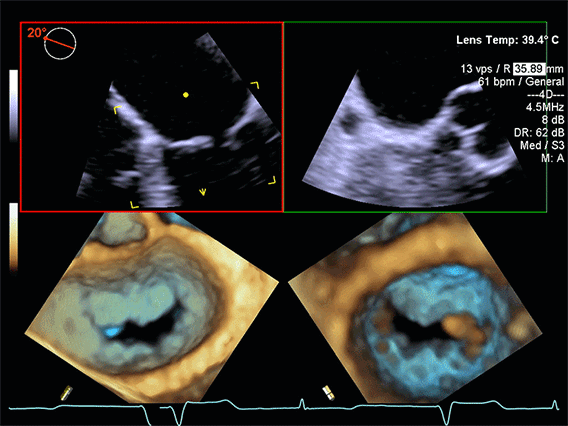

- trodimenzionalni prikaz srčanih struktura

- real-time (u stvarnom vremenu) vizualizaciju pokreta zalistaka

- preciznu procjenu anatomije i funkcije srca

4D ehokardiografija zapravo predstavlja 3D prikaz u realnom vremenu, što je posebno korisno kod kompleksnih srčanih oboljenja.

- izuzetno precizan prikaz srčanih zalistaka (mitralni, aortni, trikuspidni)